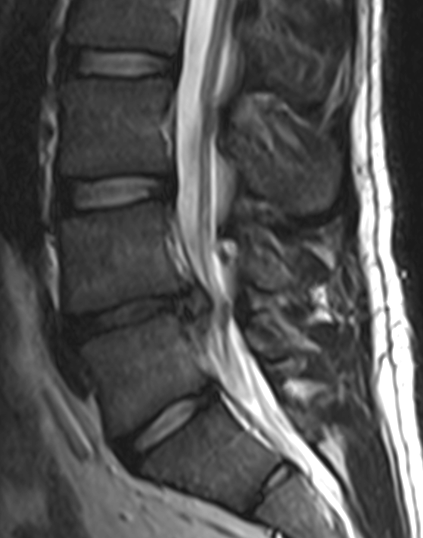

영상 검사적색 경고 징후(Red flags)가 있거나, 신경학적 증상이 호전되지 않고 지속되거나, 통증이 계속되거나 악화되는 경우에는 영상 검사가 필요하다.[3] 특히 암, 감염, 또는 마미 증후군과 같은 심각한 상태가 의심될 때는 조기에 MRI나 CT 검사를 시행하는 것이 권장된다.[3] MRI는 추간판 질환을 식별하는 데 CT보다 약간 더 우수하며, 두 검사 모두 척추관 협착증 진단에는 비슷한 유용성을 보인다.[3]

특이적 요통은 특정 질환이 원인이 되어 발생하는 요통을 의미하며, 각 질환별로 특수한 치료가 필요하다. 예를 들어, 요추의 압박 골절의 경우, 골절 부위를 일정 기간 고정하고 진통제를 투여하며, 기저 질환인 골다공증을 치료해야 할 수 있다. 경우에 따라 수술이 필요할 수도 있다.일반적으로 병력 청취와 신체 진찰을 통해 특이적 질환의 가능성을 어느 정도 배제할 수 있다. 따라서 MRI나 CT 같은 영상 진단은 만성화되었거나 치료에 잘 반응하지 않는 경우, 또는 아래에 언급될 레드 플래그 증상이 있는 경우에 고려하는 것이 보통이다.[168] 영상 진단은 암, 감염, 마미 증후군 등이 의심될 때 조기에 시행하는 것이 권장된다.[168] 추간판 탈출증 진단에는 CT보다 MRI가 약간 더 유용하며, 척추관 협착증 진단에는 두 검사 모두 유용하다.[168] 하지 직거상 검사는 추간판 탈출증 진단에 도움이 될 수 있다.[168] 지속적인 심한 요통의 원인이 되는 추간판을 특정하기 위해 추간판 조영술이 사용될 수 있으며,[175] 신경 차단술과 같은 치료적 기법이 통증 부위 파악에 도움을 줄 수도 있다.[168]